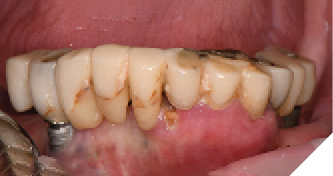

The patient returned 2 months later (due to patient scheduling delays) and the maxillary and mandibular Nexus restorations were inserted (Figs. 26A-C). Passive seating of the restorations were confirmed with the Sheffield test and radiographic confirmation. The occlusion was checked and final radiographs taken (Fig. 27).

Fig. 26A

Fig. 26B

Fig. 26C

Fig. 27